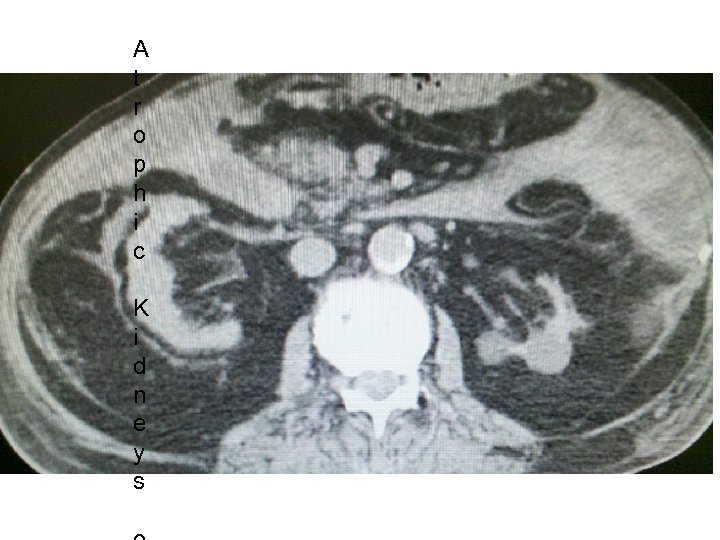

How do you differentiate ARF from CRF. • What physical exam finding tells you the pt has Chronic Kidney Disease? • What Would you see on renal Imaging for a pt with CKD?

A t r o p h i c K i d n e y s